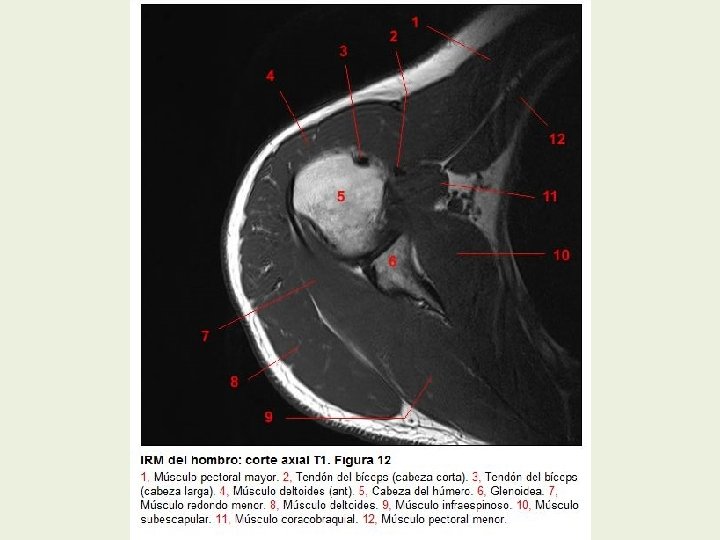

Hombro Cortes axiales RMN